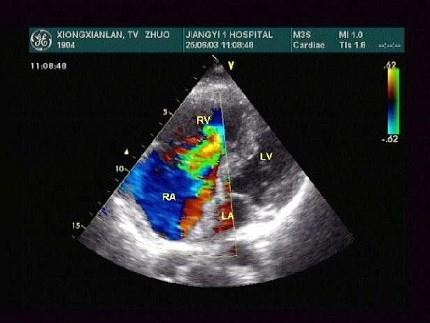

问题 男28岁,胸部疼痛1周余,神清,心律齐,超声心动图如下,根据图片应提示?(?)

选项 A.单心室 B.心内膜垫缺损 C.三尖瓣上移 D.三尖瓣下移 E.三尖瓣狭窄

答案 D